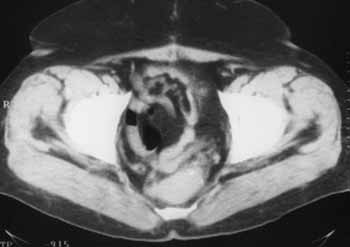

Интроскопическая диагностика рецидива рака прямой кишки.

Рис. 1. Смещение матки к крестцу через 5 месяцев после оперативного лечения по поводу рака прямой кишки. Рецидива нет.

Новости лучевой диагностики 1999 1: 21-23